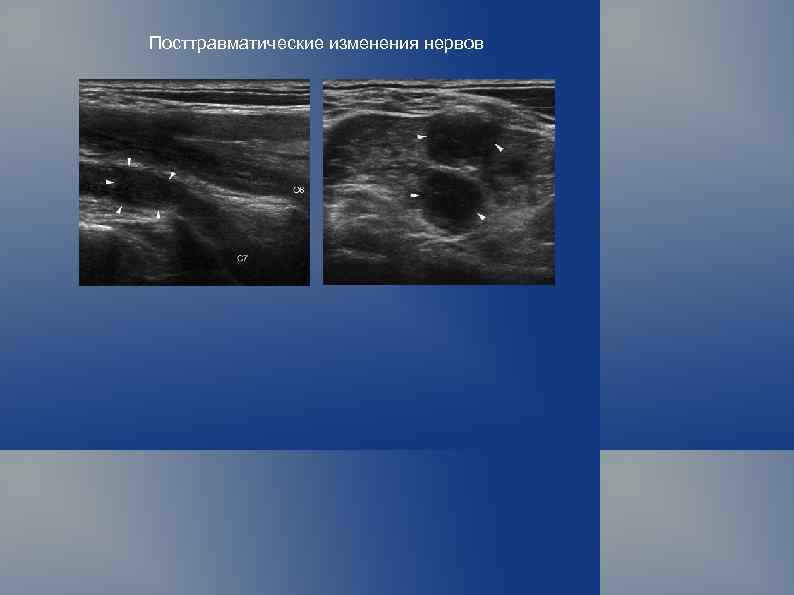

УЗ исследование периферических нервов Снижение эхогенности на фоне утолщения — являются неспецифическими проявлениями патологии.

Посттравматические изменения нервов